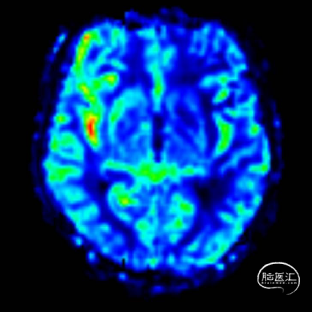

术后即刻影像。

支架植入后造影提示残余狭窄约10%。术中患者生命体征稳定,术后患者恢复良好出院,继续抗血小板聚集及他汀类药物治疗。